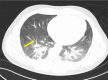

Fat embolism syndrome (FES) is a rare but serious complication most commonly associated with trauma, particularly long bone fractures. However, symptomatic FES remains a significant diagnostic and therapeutic challenge. We present the case of a 20-year-old man who, after sustaining multiple long bone fractures in a motorcycle accident and initially appearing stable, experienced a rapid and fatal progression of FES. This case underscores the unpredictable course of FES even in young, previously healthy individuals and highlights the critical need for early recognition and intervention. It also emphasizes the importance of identifying risk factors that may predict severe outcomes and mortality.